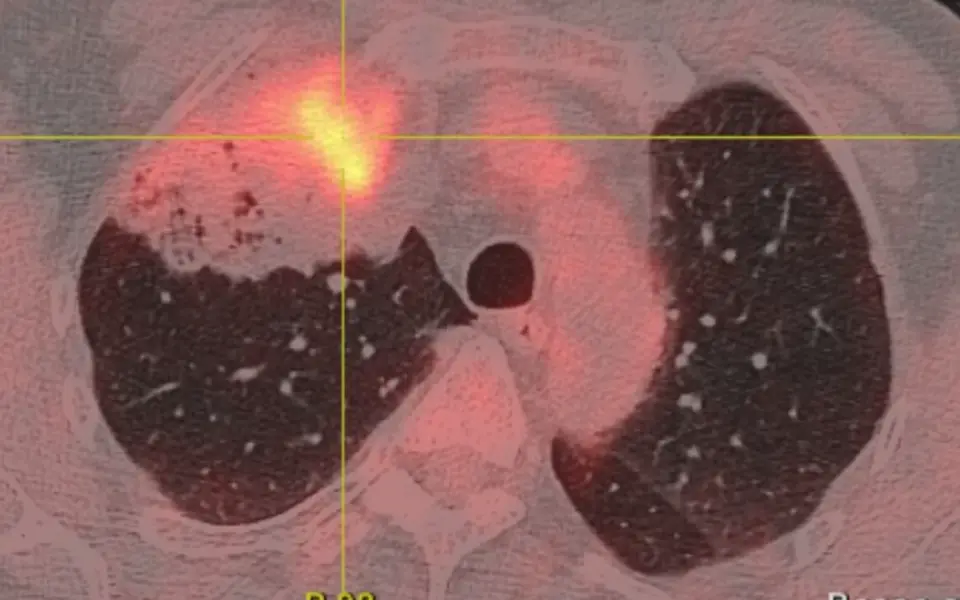

Cancérologie thoracique

Pathologies

Cancers du poumon, de la plèvre et du médiastin